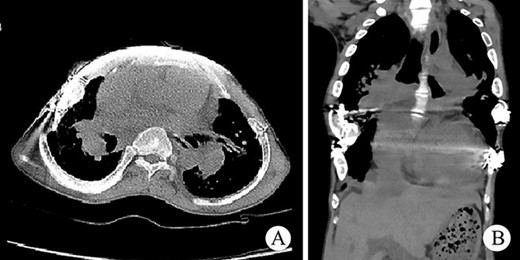

The patient was a 25-year-old man who had respiratory discomfort after birth and was diagnosed as ATD at that time. His respiratory symptoms were obvious in childhood. Hypoxia always appeared when crying but disappeared after rest. After age of 5, his condition gradually stabilized. However, after puberty, his respiratory symptoms reappeared and worsened 1 year before admission. He was admitted to our hospital for surgery finally. Physical examination showed that his thorax was narrow and small (Fig. 1A), and his height was 145 cm and chest circumference was only 63 cm. Imaging examination revealed that there were obvious depressions on both sides of the chest wall (Fig. 1B and C). The operation was carried out under general anesthesia, and performed on both sides of chest wall simultaneously. Two longitudinal incisions were performed on each sides of the chest wall respectively in the axillary midline to expose the ribs and costal cartilages. Two tunnels were made in front of the sternum but beneath the soft tissues of the anterior chest wall, and two arc-shaped steel bars were put into the tunnels, respectively. Both sides of the bars were located in front of the depressions. The structures in the depressions were lifted and fixed on the bars (Fig. 2A–C), and the depressions disappeared completely. After the incisions were closed, the operation was completed (Fig. 1D). The symptoms improved significantly, the blood oxygen saturation maintained over 92%, the chest circumference increased to 70 cm and the appearance of the chest was basically normal postoperatively. The patient was discharged 25 days after operation. Followed up for 1 year, there were no symptoms during daily activities, but there were hypoxia after vigorous activities. Imaging examination showed that the shape of the thorax was significantly improved (Fig. 3A and B).

(A) The shape of the two steel bars and the approximate position; (B) schematic diagram of operation; (C) the operation picture; and (D) thorax appearance after operation.